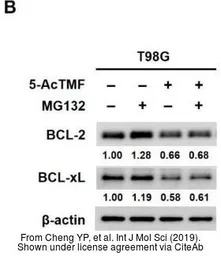

The data was published in the journal Int J Mol Sci in 2019. PMID: 31323961

The data was published in the journal Int J Mol Sci in 2019. PMID: 31323961

The data was published in the journal Int J Mol Sci in 2019. PMID: 31323961

The data was published in the journal Int J Mol Sci in 2019. PMID: 31323961